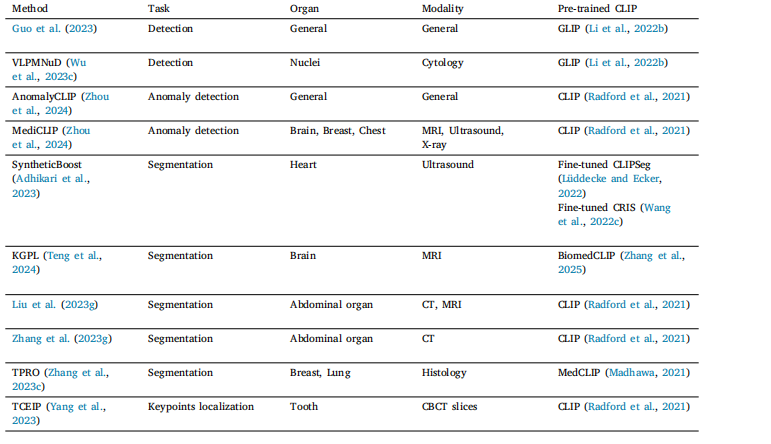

Table 4Overview of representative dense prediction applications.

表4 代表性密集预测应用概述。